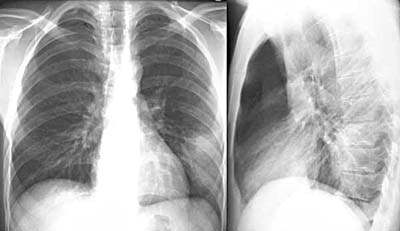

Vì bệnh có liên qua đến ổ chứa là dê và bệnh khởi phát đột ngột với hội chứng giả cúm (vì vậy có thời gian cho rằng đây là cúm dê), biểu hiện sốt cao, đau đầu, đau sau hốc mắt, đau cơ khớp, vã mồ hôi, ho, viêm hô hấp trên, ho khan, chán ăn, đau ngực, rét run, triệu chứng dạ dày ruột, tiêu chảy, đau bụng, …Sốt Q có triệu chứng ban đầu có thể gây nhầm lẫn với cúm nhưng nguyên nhân gây bệnh là khác nhau: cúm do virus còn sốt Q do vi khuẩn. Với vi khuẩn, điều trị bằng kháng sinh còn với virus cần dùng thuốc kháng virus. Có sự khác nhau về mức độ nghiêm trọng và thời gian mắc bệnh. Bệnh có thể biểu hiện không triệu chứng hoặc chỉ là thể bệnh không điển hình "sốt không rõ nguyên nhân". Ở một số trường hợp, viêm phổi được phát hiện bằng X-quang (hình ảnh mờ một phần thùy phổi hoặc một bên phổi-xem hình)) với biểu hiện lâm sàng ho, khạc đờm, đau ngực và ít có biểu hiện ral ở phổi. Kiểm tra chức năng gan thường có biến đổi. Một số trường hợp có viêm gan thể u hạt cấp và mạn tính, có thể nhầm với viêm gan do lao. Viêm nội tâm mạc mạn tính (như van hai lá động mạch chủ) hoặc van tim nhân tạo. Nhiễm khuẩn này thường không đau và kéo dài vài năm. Những hội chứng lâm sàng khác, kể cả hội chứng thần kinh ít khi xảy ra. Trường hợp bệnh cấp tính không được điều trị thì tỷ lệ chết / mắc thường dưới 1% nhưng có khi lên tới 2.4% và tỷ lệ này không đáng kể trong số những người được điều trị, trừ những trường hợp viêm nội tâm mạc điều trị bằng kháng sinh kéo dài và mổ thay van tim nhiều lần.

Sốt Q có thể gây nên tình trạng viêm nội tâm mạc (nhiễm trùng các van tim), cần thiết phải siêu âm qua đầu do thực quản mới có thể chẩn đoán được. Viêm gan do sốt Q làm tăng men gan ALT và AST, nhưng chẩn đoán xác định cần sinh thiết gan cho thấy các hình ảnh u hạt vòng trong nhu mô gan. Viêm phổi trong sốt Q cũng được chẩn đoán qua chụp X-quang khá điển hình và cần hỗ trợ các xét nghiệm khác.